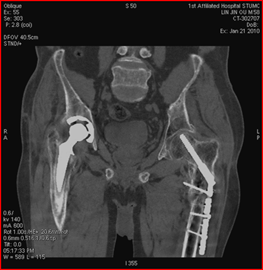

高能量X射線可以去除高密度金屬引起的偽影

常規(guī)CT 寶石能譜CT

140keV能量成像可以除去金屬引起的偽影,更加清晰觀察術(shù)后情況